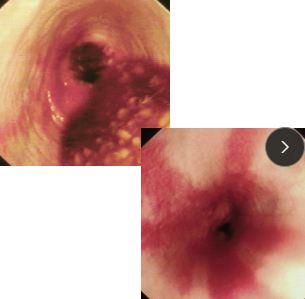

Gastroduodenal Ulcers

Et: NSAID, Steroid, GDV, MCT, renal dz, hepatic dz, sepsis

NSAIDs block PG synthesis → ↓ mucus, bicarb, blood flow → mucosal erosion

NSAID + steroid = ulcer

Cs: Hematemesis, melena, anemia, pale MM

Dt: Endoscopy (#1), regen/ iron-deficiency anemia, ↓ protein, thick mucosa

Determine GI or systemic

Tx: Fluids, (PPI) Omeprazole, Sucralfate